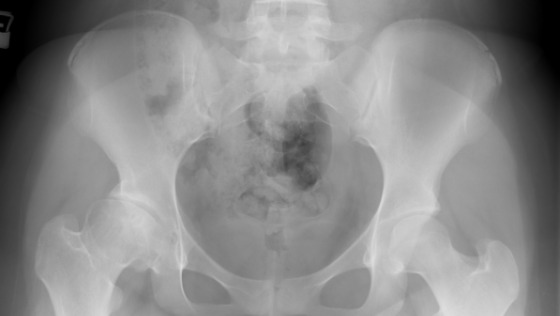

Witam.Jestem Klaudia i mam 16 lat.W moim życiu wydarzyło się wiele..Może zacznijmy od początku.W wieku 8 lat zaatakował mnie gronkowiec-uderzył w najsłabszy punkt czyli prawy staw biodrowy.Od zawsze mało jadłam i byłam strasznym chudzielcem przez co mnie dopadł.Przejdźmy do rzeczy.Któregoś pięknego dnia zaczął boleć mnie staw-stało się to dosłownie nagle.Na początku przymrużyłam na to oko bo wcześniej ćwiczyłam i myślałam że to jakieś zerwanie zwichnięcie albo po prostu zakwasy.Postanowiliśmy pojechać do lekarza.Ten obadał pomacał i przepisał jakąś maść -do dzisiaj mu za to dziękuje.. Po kilku dniach dostałam gorączki ponad 40 stopnii.W szpitalu zaraz się poznali na chorobie jednak było już za późno na leczenie farmaceutyczne.No cóż ostre zapalenie stawu biodrowego nie dało za swoje i przeszłam najpierw jedną operację-drenaż i uwalnianie się tego cholernego płynu.Wszystko fajnie kontrola 2tyg później-kolejna operacja bo się nie udało- został otwarty staw biodrowy przez co męczę się do dziś.Tyle lat po operacji i nagle zaczęło się-ból,utykanie.Po RTG nogi:Głowa kości udowej zniekształcona z geodami,przemieszczona ku górze i bocznie.Zwężenie szpary stawowej w kwadrantach górnych,sklerotyzacja nadchrzęstna i nadbudowa stropu panewki w stawie biodrowym prawym.Dzisiaj męczę się z postępującym zwyrodnieniem- choroba która "łapie" ludzi w podeszłym wieku.. a ja mam dopiero 16 lat i nawet nie wyobrażam sobie,że będę miała sztuczny staw albo skończę na wózku.Chciałabym mieć dzieciństwo jak każdy inny człowiek jednak mój los od samego początku plata mi figle.Będę wdzięczna za każdą złotówkę i dziękuję za spędzony czas na czytaniu tego.